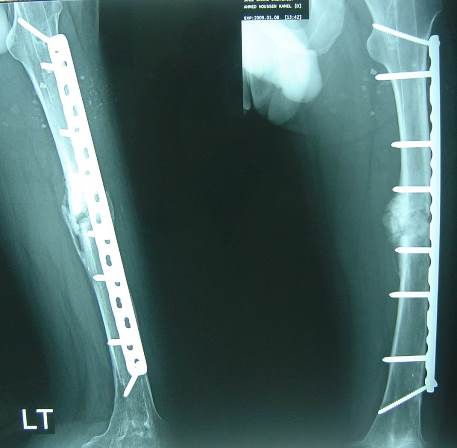

Perioperative data:

Operative time: 4 hours nail removal + 2 hours plate insertion.

Blood loss: 2000cc, 3 units transfused.

Middle part of the nail was removed by a small break in the lateral cortex.

Distal part of the nail was removed by a hole distally in the lateral cortex then pushed by a drill pit and pulled through the medulla by an intestinal clamp.

Bone graft.

No infection postoperative.

4 months later